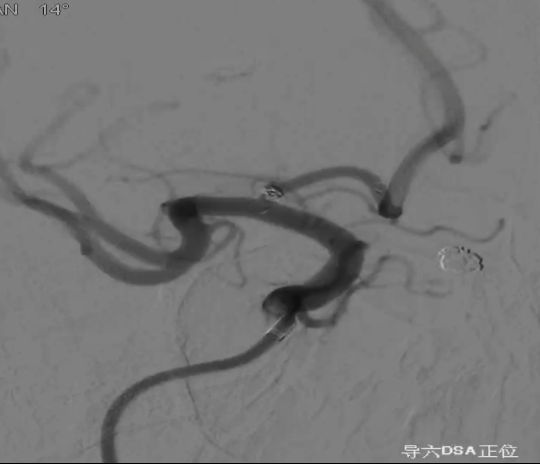

治疗结果

术后正侧位造影:Raymond Ⅲ级

术后支架重建:支架打开良好,近端Marker位于颈内动脉分叉处

继续填入Target 1.5/2弹簧圈成篮,后完全释放支架,其近端位于颈内动脉分叉处,远端位于A1远端。

通过调整栓塞微导管的张力继续填入Target 1/3弹簧圈。